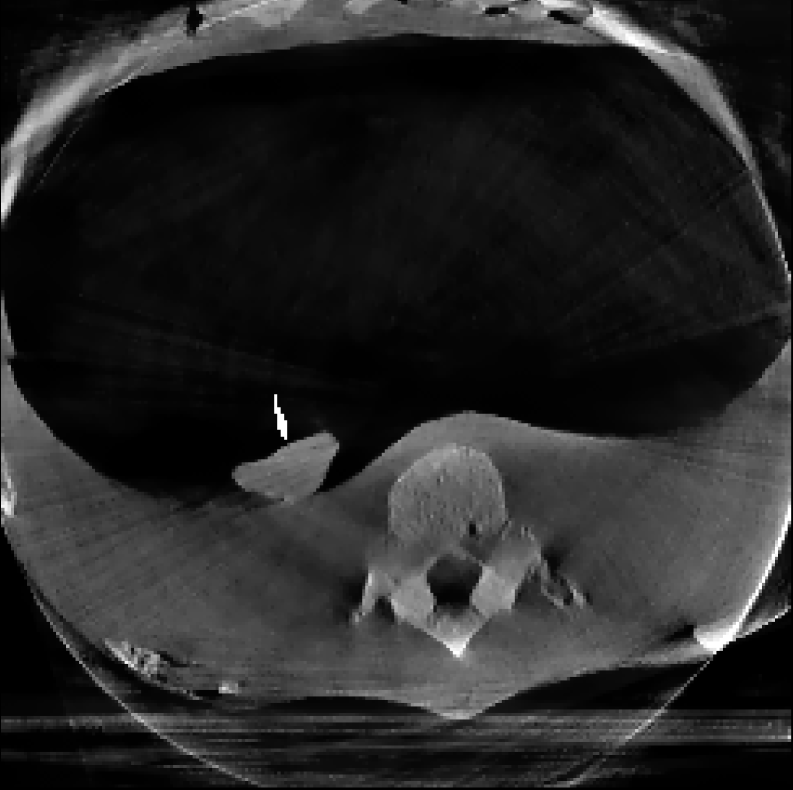

The reconstructions corresponding to the real-scan data with different number of projections (180, 50, and 20, respectively), can be observed in Figures 3, 4, and 5. In all three figures (a) is the prior image 𝒙p\boldsymbol{x}_{p} used for prior image regularization, (f) is the ground truth image; and the rest of images correspond to different reconstructions (top) with their corresponding errors (bottom). Analogously to the previous experiment, the difference images (or error) should be completely black in the case of a perfect reconstruction and high intensity indicates more inaccurate reconstructions.

Note that the real data contains a lot of measurement noise, and due to the presence of the needle, the reconstructions can suffer from strong metal artifacts. Therefore, the reconstructed images using different algorithms, particularly without explicit regularization, tend to show strong errors even with a high number of projections. Accordingly, all the algorithms with explicit regularization perform better in this scenario, and particularly those including PIPLE or PICCS regularization. Moreover, the proposed IRN-PIPLE algorithm significantly outperforms other methods, and IRN-PICCS is not far behind. Using only TV regularization struggles to separate artifacts from features, oversmoothing images and thus loosing important image features. Notably, the proposed methods reconstruct high quality images in less than 2 minutes in an implementation that is not optimized to solve this specific geometry.

Figure 4: Reconstructed images using real measurements of a thorax phantom with 50 projection. The reconstructed images are shown in [0, 0.03]; difference images in [–0.04, 0.04].